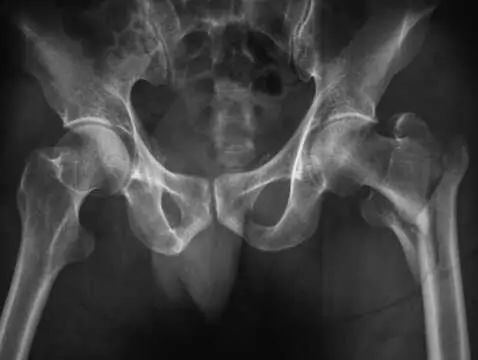

Una hernia inguinal es el desplazamiento de parte del contenido abdominal a través del anillo inguinal superficial.